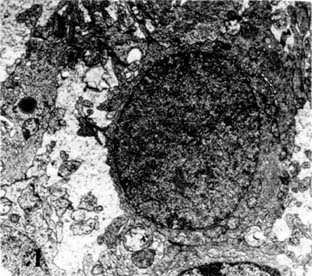

Β) Τόσο εντός των κυττάρων όσο και εντός των προσεκβολών παρατηρούνται πολυάριθμες νευρογλοιακές ίνες που σχηματίζουν πυκνές δέσμες και αποτελούν το παθογνωμονικό κριτήριο των αστροκυττωμάτων (Εικ. 1).

Ε) Τα νεοπλασματικά κύτταρα παρουσιάζουν κατάτμηση των μικροσωληναρίων ενώ τα διάμεσα ινίδια εναποτίθενται σε παράλληλες δέσμες. Φέρουν δε σπανίως πινοκυτταρικά κυστίδια στην ελεύθερη επιφάνειά τους. (Εικ. 2, 3).